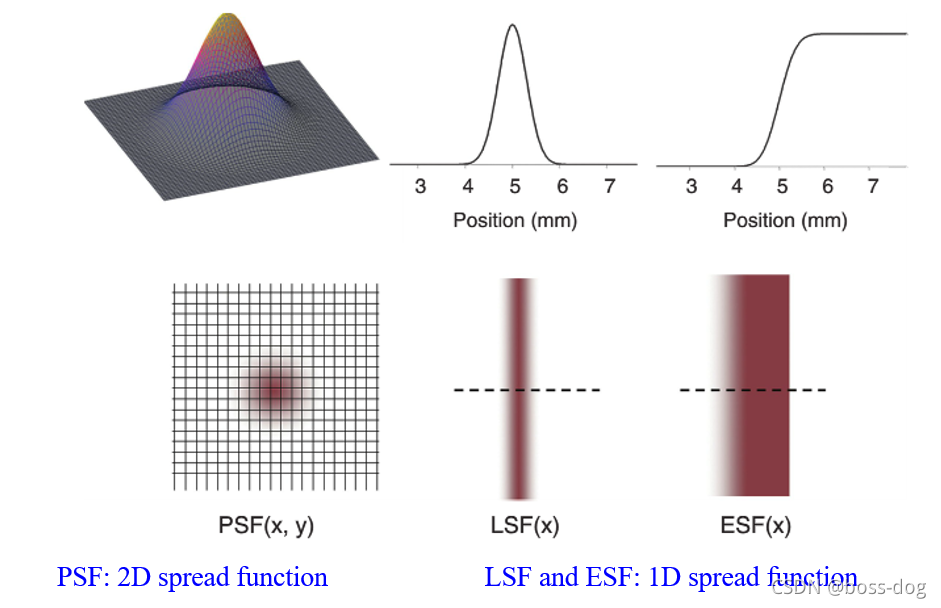

分辨率

复合成像系统的MTF

任何成像系统的MTF都是该系统各部件MTF的乘积。在每毫米5个周期的空间频率下,x射线胶片-屏幕成像系统各部件的MTF为焦斑0.9,运动0.8,和强化屏幕0.7。

则复合成像系统的MTF为0.9 × 0.8 × 0.7=0.5。